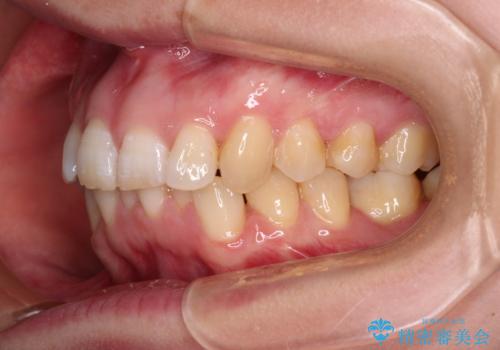

カリエールディスタライザーや部分的なワイヤー矯正を併用したことで、確実かつ短期間で治療を終えることができました。